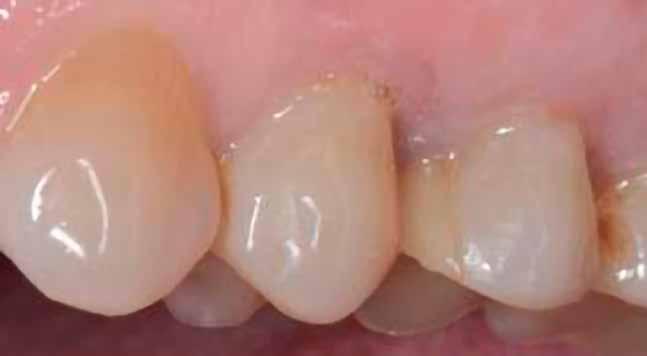

A periimplantáris lágyszövetekben, a végső klinikai képen, irritációra utaló jel nem látható, a keratinizált íny szélessége kielégítő.

25. ábra: A végleges fogpótlás átadása. – 26. ábra: A végleges fogpótlás okkluzális nézetből.

Az itt bemutatott protokoll lehetővé teszi a vertikális csontdefektusok biztonságos rekonstrukcióját, pusztán autológ csont felhasználásával, valamint a protetikai, esz-

tétikai és funkcionális rehabilitációt egy rögzített, implantátumon elhorgonyzott, átmenő csavaros fogpótlással.